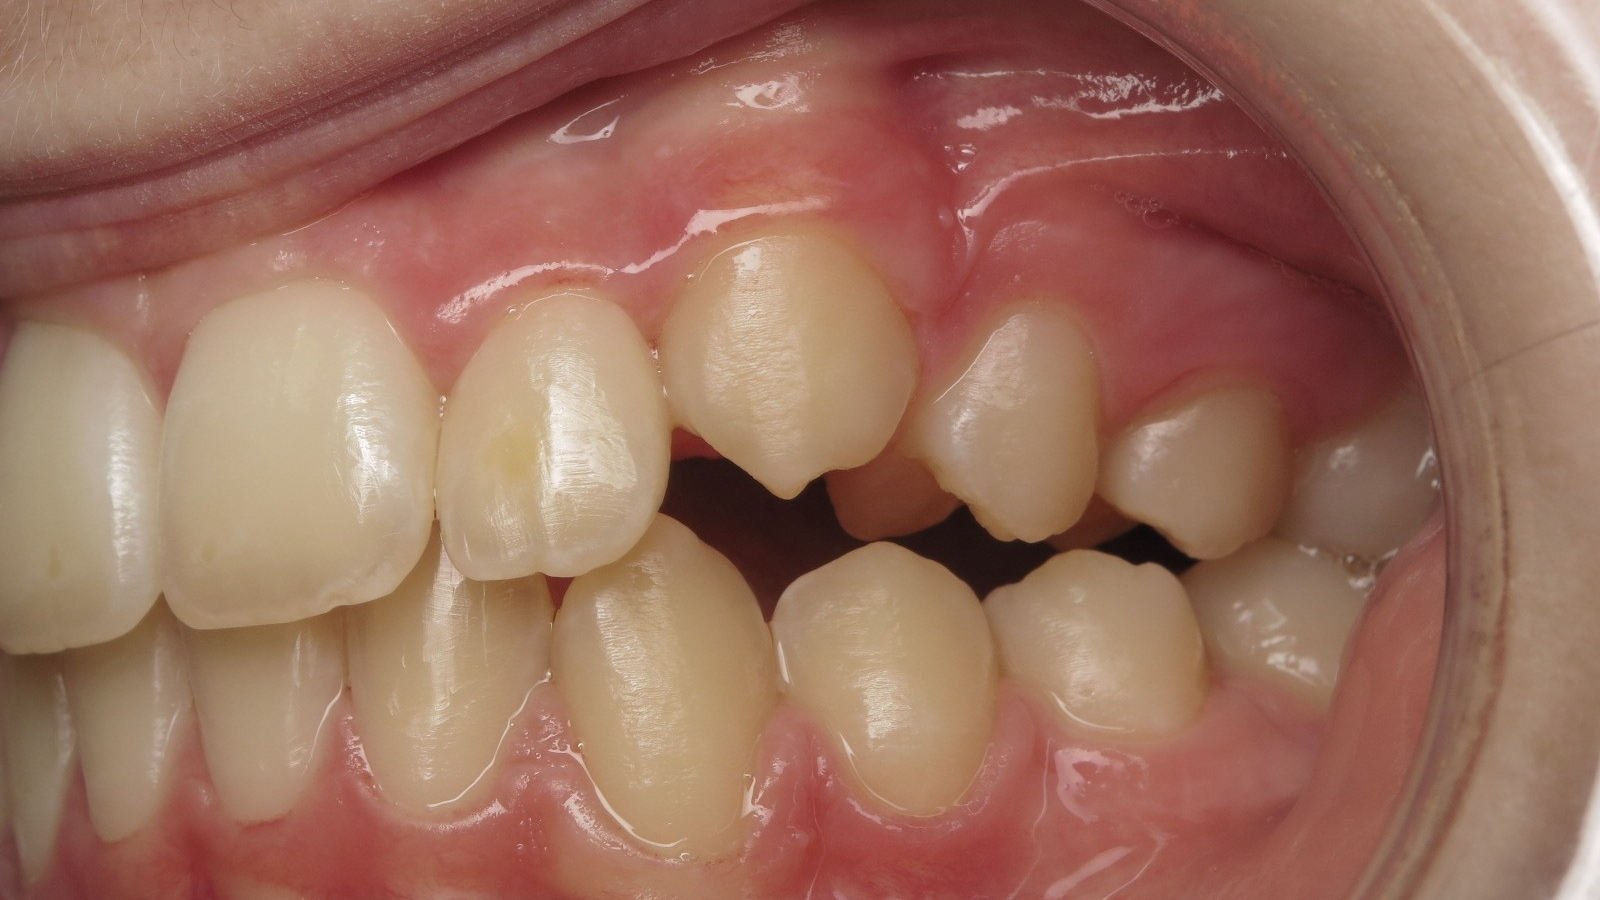

Décalage entre les dents d avant en arrière

surveillance évolution de la dentition pendant 4 ans

bilan début fin de traitement